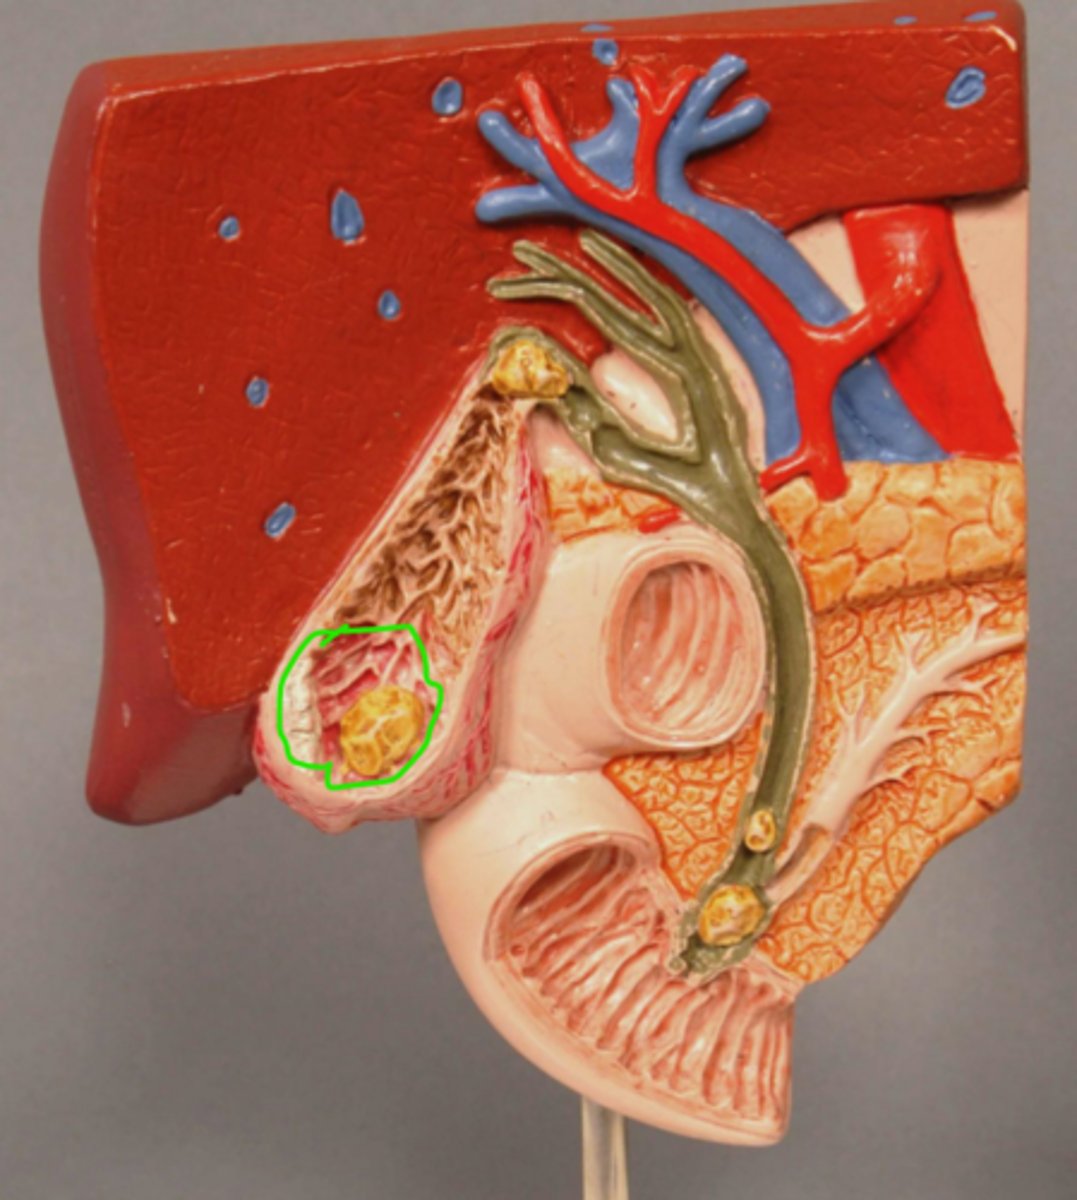

Gallstone in Fundus of Gallbladder